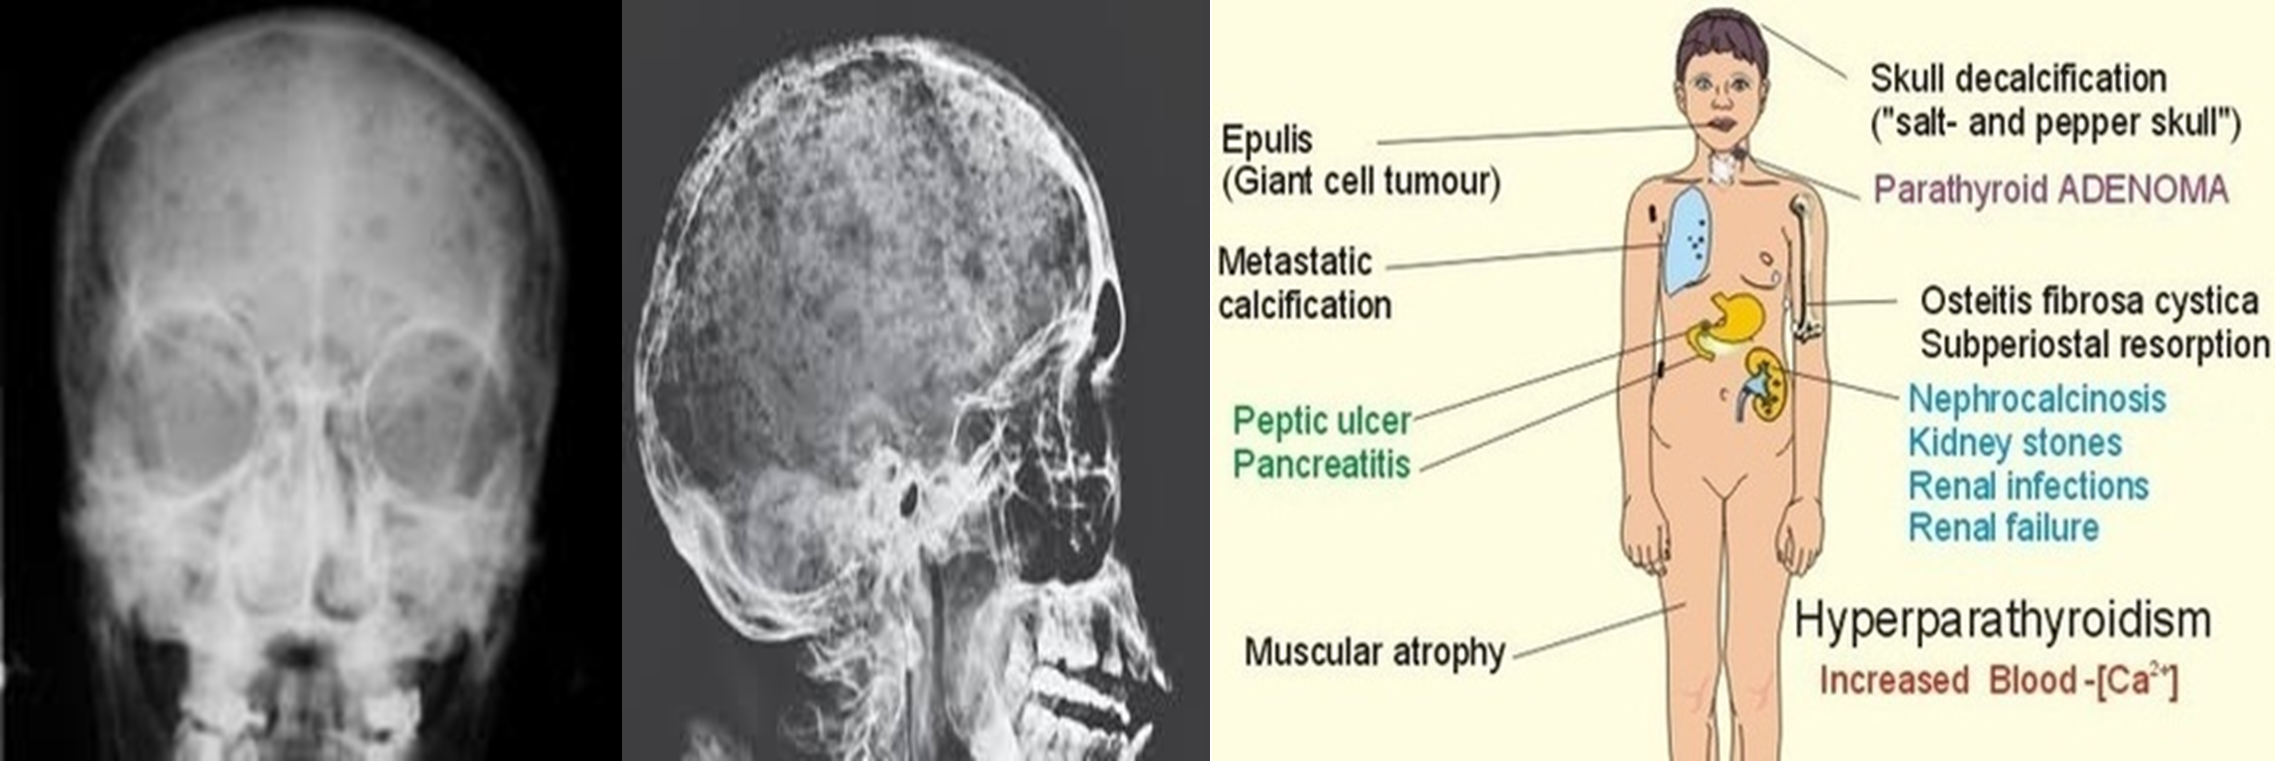

Hyperparathyroidism

Effects of Increased PTH ✓

Clinical Manifestations: “Bones, Stones, Moans, Groans”

Bones

- Rarefaction (decreased bone density)

- Brown tumors

- Sub-periosteal resorption of:

- Middle phalanges

- Lateral end of clavicle

- Skull: “salt & pepper” appearance

- Soft tissue calcification

Stones

- Kidney stones and nephrocalcinosis

Moans

- Abdominal pain

- Renal pain

Groans

- Psychological manifestations: depression, stress

Clinical features

- Older women, >40 years of age.

- Renal calculi or renal calcification – occurs in 20% of patients, polyuria (‘renal stones’).

- Bone pain or deformity, osteitis fibrosa cystica, pathological fractures (‘painful bones’).

- Muscle weakness, anorexia, intestinal atony, psychosis (‘psychic moans’).

- Peptic ulceration and pancreatitis (‘abdominal groans’).

Salt-and-pepper-spots-in-skull